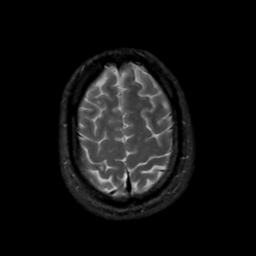

MR Study #14, June 2, 1991 -- Slice #42